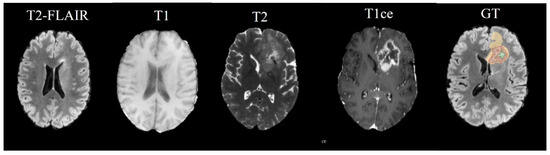

Considering the constrained three-dimensional resolution within the BRATS dataset, this study introduces a methodical segmentation technique that meticulously evaluates each pixel in concert with its corresponding MRI modalities T1, T2, T1ce, and T2-FLAIR to ascertain pixel classification. This approach aligns with the operational paradigm of contemporary U-Net-based segmentation models, where pixel classification is predicated on the multi-modal neighborhood analysis in Figure 1.

BRATS21 is a large-scale brain multimodal MR Glioma segmentation dataset, including 8160 MRI scans from 2040 patients. Among them, 1251 cases of data were used as training sets and publicly labeled, while 219 cases of data were divided into validation sets and 570 cases of data were used as test sets. MR Images are given for each patient in four modalities in Figure 4.

• Native (T1) scans;

• Post-contrast T1-weighted scans with Gadolinium (T1Gd);

• T2-weighted (T2) scans;

• T2 Fluid Attenuated Inversion Recovery (T2-FLAIR) volumes.

Figure 1. Schematic representation illustrating the sequential processing of MRI modalities T1, T2, T1ce, and FLAIR, as implemented in our segmentation approach for pixel classification within the context. Different colors represent the same region of different modalities.

Figure 4. The first four images from left to right show the MRI modalities used as input channels to various Arouse-Net models and the fifth image shows the ground truth labels. The enhanced tumor (ET) from edema/necrotic tissue (ED) is differentiated and the necrotic tumor core (NCR) is delineated within the complexities of medical image segmentation.